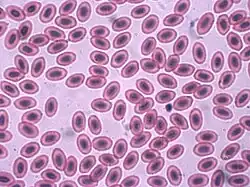

In non-mammals

Human blood is typical of that of mammals, although the precise details concerning cell numbers, size, protein structure, and so on, vary somewhat between species. In non-mammalian vertebrates, however, there are some key differences:[19]

- Red blood cells of non-mammalian vertebrates are flattened and ovoid in form, and retain their cell nuclei.

- There is considerable variation in the types and proportions of white blood cells; for example, acidophils are generally more common than in humans.

- Platelets are unique to mammals; in other vertebrates, small nucleated, spindle cells called thrombocytes are responsible for blood clotting instead.